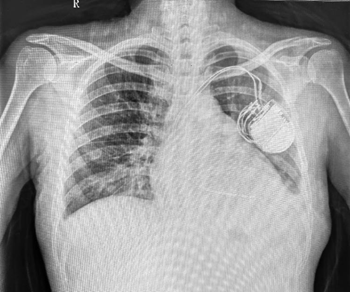

2023年5月5日,江西省人民医院(南昌医学院第一附属医院)-省心血管病医院六科成功为一反复发作意识丧失、室性心动过速患者植入双腔复律除颤器。患者在新医保报销政策落地和起搏器带量采购的双重利好政策下,享受到了优质廉价的医疗服务。

入院后完善彩超、心电图诊断等相关检查后诊断:室性心动过速、高血压、2型糖尿病、慢性肾脏病5期、Q-T间期延长,肝功能不全。省心血管病医院起搏器团队刘元庆副主任医师指出患者存在ICD植入适应症,告知患者及家属手术必要性、风险及费用后,同意手术,随即择期为患者行心脏复律器或除颤器的植入术。

术后患者生命体征稳定,5月8日和10日行血透治疗,未再出现心脏骤停。术后患者自付费用仅为3万元左右,这都得益于近期一些列医改惠民政策在江西省人民医院的落地。2023年4月25日,起搏器带量采购正式执行,执行后起搏器耗材费用大幅下降,最大降幅76.13%。同时江西省已于4月1日执行新的医保报销政策,新医保政策执行后起搏器报销额度由原来的1.5万限额提升到单次住院10万限额,医保报销后起搏器类耗材患者自付金额在2万元左右,ICD和CRTP/D类耗材患者自付金额在3-5万元左右。